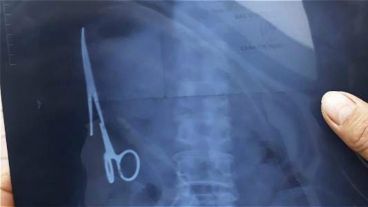

El hombre, identificado como Ma Van Nhat de 54 años, tuvo un accidente de tránsito, y cuando le hicieron una radiografía, descubrieron un instrumento de 15 centímetros de largo en la parte izquierda del estómago. El mismo se encontraba oxidado en las puntas.

Lo increíble es que el paciente nunca había sentido molestias, y recordó que las tijeras debían haber quedado en su interior en una operación que le realizaron en junio de 1998 en el Hospital General Bac Kan, justamente por otro accidente de tránsito.